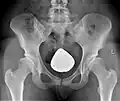

Diagnostik

Sowohl zur genauen Beurteilung der Hüftdysplasie und ihres Schweregrades, als auch zur Planung der Operation werden konventionelle Röntgenbilder des Beckens, sogenannte Beckenübersichtsaufnahmen, angefertigt.

Computertomographien (CT) oder Magnetresonanztomographien (MRT) sind nur in Ausnahmefällen notwendig, um z. B. den Grad der Gelenkschädigung besser beurteilen zu können. Computerverfahren zur dreidimensionalen Darstellung von Organen haben sich im Bereich des Beckens nicht etabliert. Jedoch kommt das 3D-CT des Beckens bei CT-gestützten Navigationsverfahren (siehe unten) zum Einsatz.[7]

Nachbehandlung und Rehabilitation

In den ersten vier bis sechs Wochen liegen die Schwerpunkte der Nachbehandlung in der Mobilisierung des Patienten und ggf. einer Schmerztherapie. Das Bein der betroffenen Seite darf während dieser Zeit nicht oder nur sehr wenig belastet werden. Die Patienten müssen dabei lernen an Unterarmgehstützen oder mittels anderer Gehhilfen zu gehen. Weiterhin übt der Patient unter physiotherapeutischer Anleitung ein, wie er sitzen und aufstehen muss. In den folgenden Wochen wird in einer stationären oder ambulanten Anschlussheilbehandlung die Belastung des betroffenen Beines langsam und stetig aufgebaut, nicht zuletzt um die Muskulatur zu kräftigen. Auch das Treppensteigen und andere alltägliche Bewegungsabläufe müssen in der Zeit bis zum Erreichen der vollen Belastungsfähigkeit neu einstudiert werden. Zur Kontrolle des Heilungsprozesses der Knochen werden in regelmäßigen Abständen weitere Röntgenaufnahmen des Beckens angefertigt.[7] Die Dauer und der detaillierte Ablauf der Nachbehandlung variieren je nach Operateur sowie individuellen Faktoren.